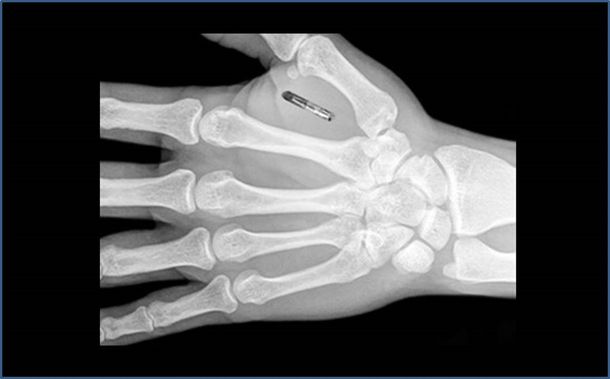

Aunque el chip se puede disimular en cualquier parte del cuerpo, lo más práctico es inyectarlo en la mano, en la zona entre el dedo índice y el pulgar. La moda actual dicta que lo ideal es llevar dos: uno en cada extremidad. Su precio oscila entre los $ 400 y los $ 1.200.